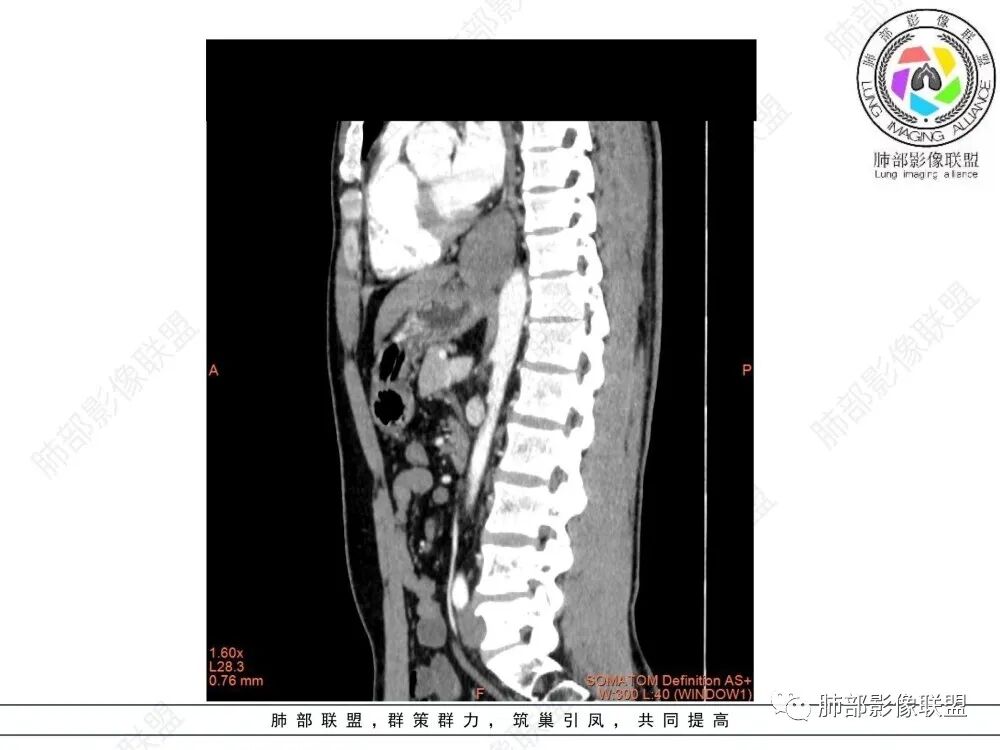

食管下段肿块,环壁生长,分叶状,密度比较均匀,钡餐造影食管下段弧形受压移位,并可见龛影,考虑为食管平滑肌瘤或食管结核。

后面造影图,像腔外  南边老师看得仔细

造影虽然像外压,但是ct肯定更清楚,看ct就是一个环绕管壁生长,管腔狭窄,定位应该没有问题,但是大家病理都答对了,太厉害了

食管平滑肌瘤是最常见的食管良性肿瘤,多见于男性,男女之比为2.6:1,高发年龄 30~60岁之间与食管癌相比,食管平滑肌瘤 的一个主要特点是病史相对较长,病情进展缓慢。病史最长者达10年余,平均 15.7个月,尽管病史较长,但大多数患者仍能进普食。食管平滑肌瘤的诊断一般比较容易,结合患者临床症状、食管造影及食管镜所见,一般均能得出正确诊断。食管造影主要为充盈缺损,病变与食管壁成锐角,粘膜线连续无破坏,管腔收缩扩张比较自如。钡餐造影敏感性高,但对食管壁间及食管周围情况难以判断。CT具有极高的密度分辨率,并且可以获得高质量的多平面重组图像,有利于食管壁间及食管周围情况的判断,表现为食管下段环绕管壁生长,偏心性或薄厚不均软组织密度肿块,密度均匀,内缘分叶状,管腔与正常食管壁构成不规则多角形扩张,增强动脉期无强化,多角度重建其病灶长轴与食管长轴不一致。由于食管壁在收缩状态下厚度约为5.6mm,扩张状态厚度不超过3mm,CT扫描时保持食管处于扩张状态可提高小病灶检出率。MR表现为T1加权等信号,T2加权稍高信号,可见高信号粘膜层,增强扫描轻度渐进性强化,密度均匀,无出血坏死。对于粘膜及周围脂肪间隙的判断具有明显优势。